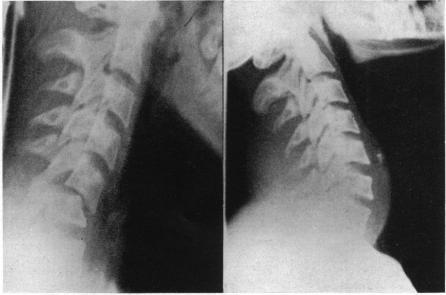

SKELETAL TRACTION IN THE TREATMENT OF FRACTURES AND DISLOCATIONS OF THE CERVICAL SPINE.

Ann Surg. 1937 Oct;106(4):770-6. doi: 10.1097/00000658-193710000-00026.